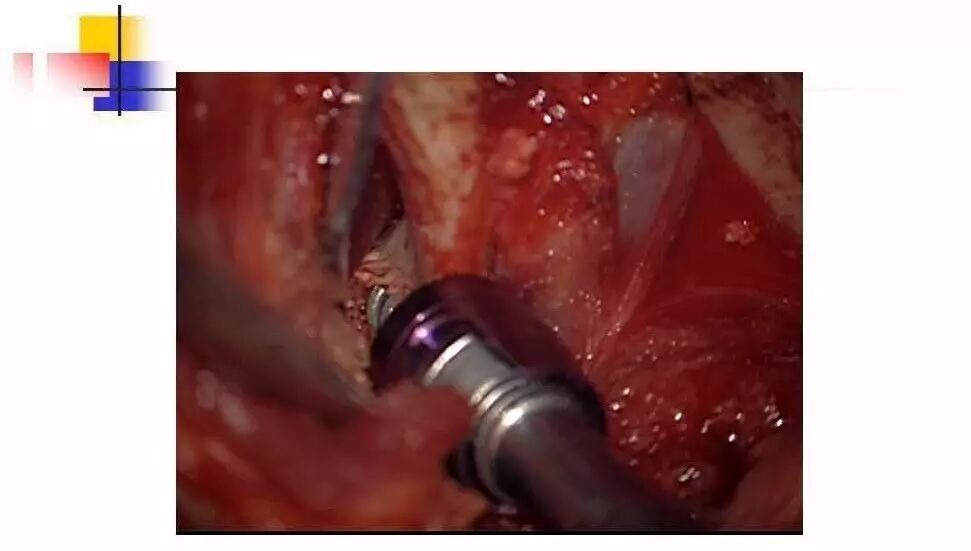

在脊柱神经外科、显微神经外科和颅底肿瘤外科前沿研究和临床诊治领域有着扎实的基础,为全国首批获得脊柱神经外科医师培训认证的神经外科医生。擅长颈椎病、椎管肿瘤及各种脊柱疑难疾病的诊治、脑肿瘤微创手术,尤其擅长颈椎退行性疾病的手术,率先在国内开展了颅底凹陷后路复位、颈前路减压融合等高难度手术,多年来收治了来自全国各地的大量患者,疗效达到国内领先水平。